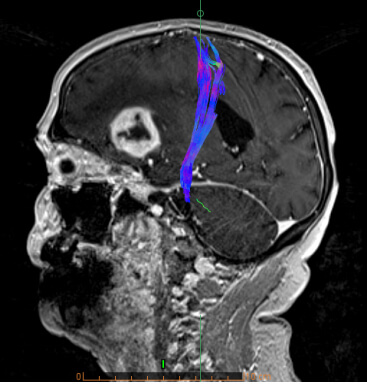

- Ενσωμάτωση των δεδομένων σε συστήματα νευροπλοήγησης, ώστε ο νευροχειρουργός να αποφεύγει κατά την διάρκεια του χειρουργείου τα λειτουργικά κέντρα του εγκεφάλου (π.χ. κέντρο λόγου και κίνησης) και τη μόνιμη νευρολογική βλάβη

- Δεσμιδογραφία (Τractography)